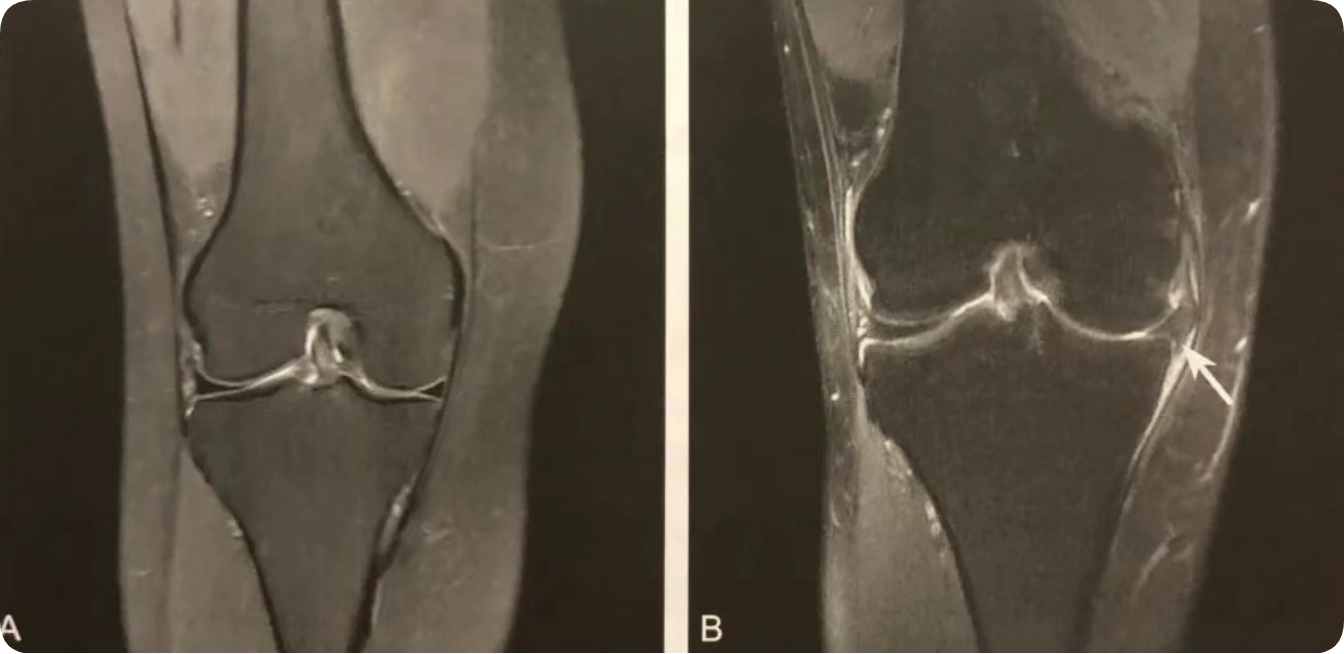

1. 半月板移位的直接征象;

2. 在膝关节 MRI 冠状位半月板体部的中央平面观察;

3. 半月板外缘超过胫骨平台关节面边缘 ≥3mm ;

4. 常伴半月板复杂撕裂或膝关节支持系统损伤,应注意观察。